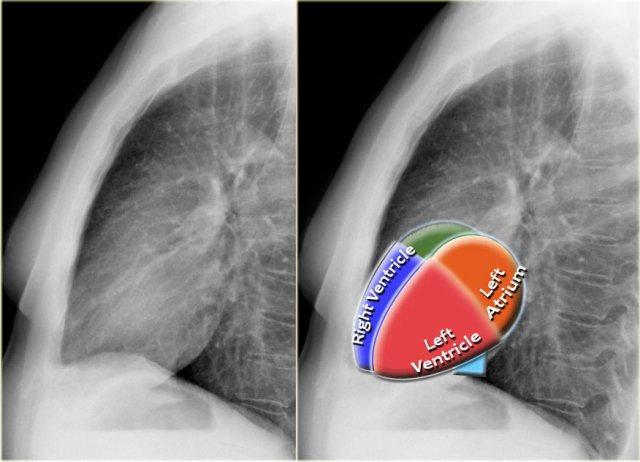

Tư thế nghiêng

Trên phim X-quang ngực tư thế nghiêng, các bờ tim cần được xác định rõ ràng, và tĩnh mạch chủ dưới (IVC) thường có thể thấy đổ vào nhĩ phải.

Khoang sáng sau xương ức

Khoang sau xương ức bình thường chứa phổi có khí và do đó phải có hình ảnh thấu quang (tối trên phim), kéo dài xuống dưới đến mức thất phải tiếp xúc với xương ức (mũi tên đen nhỏ).

Bất kỳ hình mờ nào trong khoang sau xương ức phía trên đều đáng ngờ về tổn thương trung thất trước hoặc khối xuất phát từ các thùy trên của phổi.

Dấu hiệu cột sống

Khi đánh giá các thân đốt sống trên tư thế nghiêng, chúng phải có hình ảnh thấu quang (tối hơn) tăng dần từ trên xuống dưới do lượng phổi có khí chồng lên ngày càng nhiều (mũi tên trắng).

Nếu các đốt sống ngực dưới có hình ảnh đậm bất thường, điều này có thể gợi ý bệnh lý ở các thùy dưới, chẳng hạn như đông đặc hoặc khối — đây được gọi là dấu hiệu cột sống.

Đánh giá Cơ hoành

- Vòm hoành phải phải được nhìn thấy rõ ràng ở phía trước đến tận thành ngực (mũi tên đỏ), thể hiện ranh giới giữa phổi có khí và mô mềm ổ bụng.

- Vòm hoành trái thường chỉ nhìn thấy đến điểm tiếp giáp với bóng tim (mũi tên xanh lam), phía ngoài điểm đó ranh giới bị mất do tỷ trọng tương đương giữa tim và các tạng bụng phía trên.

Bờ Từng Buồng Tim trên Tư Thế Nghiêng

- Nhĩ Trái: Tạo thành bờ tim sau-trên; giãn gây phồng ra phía sau.

- Thất Trái: Tạo thành bờ tim sau-dưới; giãn gây di lệch ra sau-dưới.

- Thất Phải: Chiếm khoang sau xương ức phía dưới; giãn lấp đầy khoang sáng sau xương ức theo hướng từ dưới lên trên.

Giải Phẫu Van Tim trên X-quang Tư Thế Nghiêng

- Để xác định vị trí các van tim trên tư thế nghiêng, vẽ một đường từ carina đến mỏm tim:

- Phía trên đường: Van động mạch chủ và van động mạch phổi

- Phía dưới đường: Van ba lá và van hai lá (4)

Đường kẻ này giúp ước lượng vị trí các van tim và đánh giá tình trạng giãn từng buồng tim.

Lưu ý hình ảnh giãn thất trái mức độ nặng trên tư thế nghiêng này.